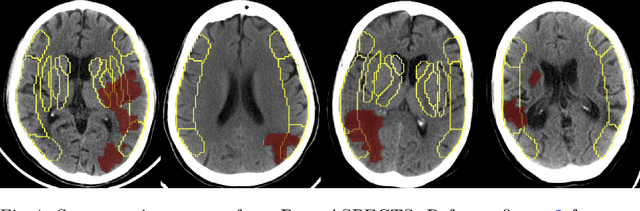

Abstract:A stroke occurs when an artery in the brain ruptures and bleeds or when the blood supply to the brain is cut off. Blood and oxygen cannot reach the brain's tissues due to the rupture or obstruction resulting in tissue death. The Middle cerebral artery (MCA) is the largest cerebral artery and the most commonly damaged vessel in stroke. The quick onset of a focused neurological deficit caused by interruption of blood flow in the territory supplied by the MCA is known as an MCA stroke. Alberta stroke programme early CT score (ASPECTS) is used to estimate the extent of early ischemic changes in patients with MCA stroke. This study proposes a deep learning-based method to score the CT scan for ASPECTS. Our work has three highlights. First, we propose a novel method for medical image segmentation for stroke detection. Second, we show the effectiveness of AI solution for fully-automated ASPECT scoring with reduced diagnosis time for a given non-contrast CT (NCCT) Scan. Our algorithms show a dice similarity coefficient of 0.64 for the MCA anatomy segmentation and 0.72 for the infarcts segmentation. Lastly, we show that our model's performance is inline with inter-reader variability between radiologists.